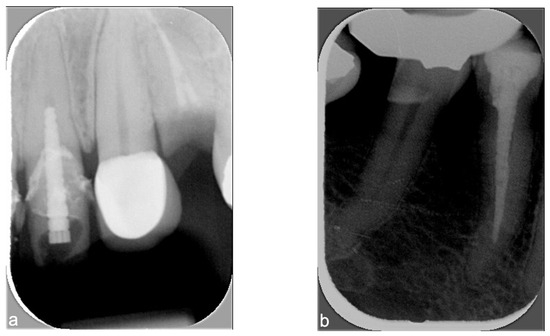

- Deniz, Y.; Kaya, S. Determination and classification of intraoral phosphor storage plate artifacts and errors. Imaging Sci Dent. 2019, 49, 219–228. [Google Scholar] [CrossRef] [PubMed]

- Patel, J.R. Intraoral radiographic errors. Oral Surg. Oral Med. Oral Pathol. Oral Radiol. 1979, 48, 479–483. [Google Scholar] [CrossRef] [PubMed]

- Elkhateeb, S.M.; Aloyouny, A.Y.; Omer, M.M.S.; Mansour, S.M. Analysis of photostimulable phosphor image plate artifacts and their prevalence. World J. Clin. Cases 2022, 10, 437–447. [Google Scholar] [CrossRef] [PubMed]

- Bedard, A.; Davis, T.D.; Angelopoulos, C. Storage phosphor plates: How durable are they as a digital dental radiographic system? J. Contemp. Dent. Pract. 2004, 5, 57–69. [Google Scholar] [CrossRef] [PubMed]

- Ruiz, D.C.; Gomes, A.F.; Fontenele, R.C.; Haiter-Neto, F.; Freitas, D.Q.; Groppo, F.C. Could the radiographic image quality be affected by the excessive use of the photostimulable phosphor plate? Braz. Dent. J. 2023, 34, 39–44. [Google Scholar] [CrossRef] [PubMed]

- Souza-Pinto, G.N.; Santaella, G.M.; Coli, A.A.; Oenning, A.C.; Haiter-Neto, F. Analysis of the deterioration of photostimulable phosphor plates. Dentomaxillofacial Radiol. 2020, 49, 20190500. [Google Scholar] [CrossRef] [PubMed]